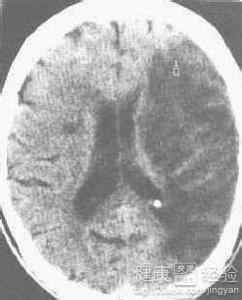

腔隙性腦梗塞還是屬於腦血管性疾病的,只不過腔隙性腦梗塞是屬於微動脈梗塞造成的大腦小部分區域的梗塞灶,一般除非是腦干的腔梗,都還是比較輕微的,一般症狀有頭暈頭痛、肢體麻木、眩暈、記憶力減退、反應遲鈍、抽搐、癡呆,無意識障礙,精神症狀少見。可能發病的原因有高血壓導致的血管變脆,高血脂引起動脈粥樣硬化,血管內一些小栓子脫落堵塞腦血管造成的